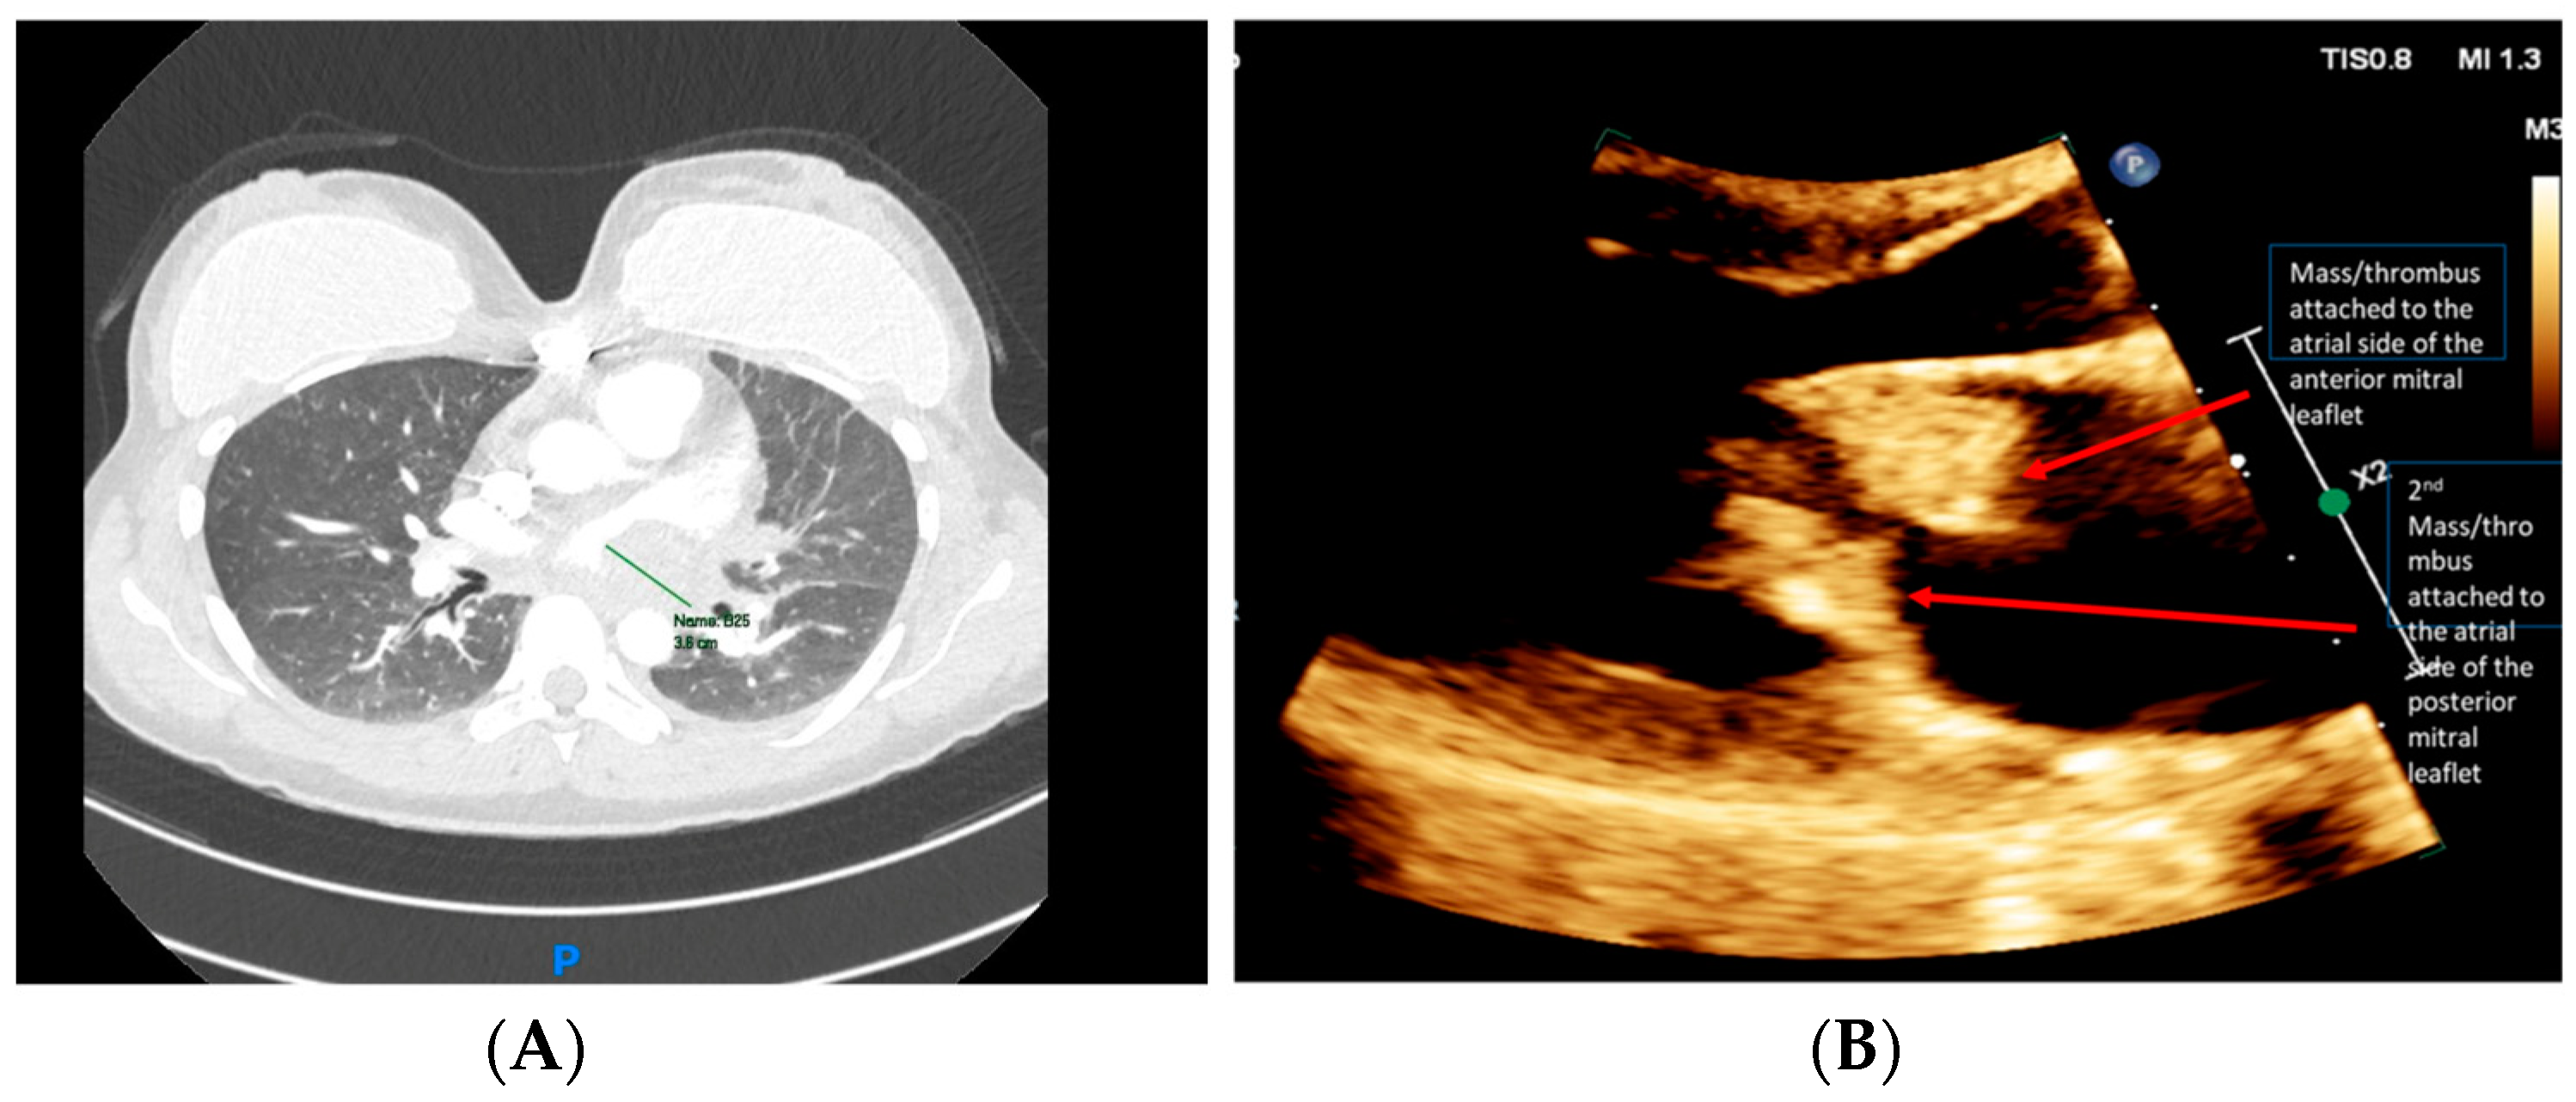

A chest computed tomography angiography (CTA) was performed, which did not demonstrate evidence of PE. The imaging revealed a large left atrial (LA) filling defect, with signs of pulmonary hypertension (

Figure 2A). Transthoracic echocardiogram (TTE) demonstrated multiple mobile mitral valve masses (anterior and posterior), mostly on the atrial side, 29 × 16 mm in size, prolapsing into the left ventricle (LV) and causing severe functional mitral stenosis (MS), mitral regurgitation (MR), and pulmonary hypertension (

Figure 2B).